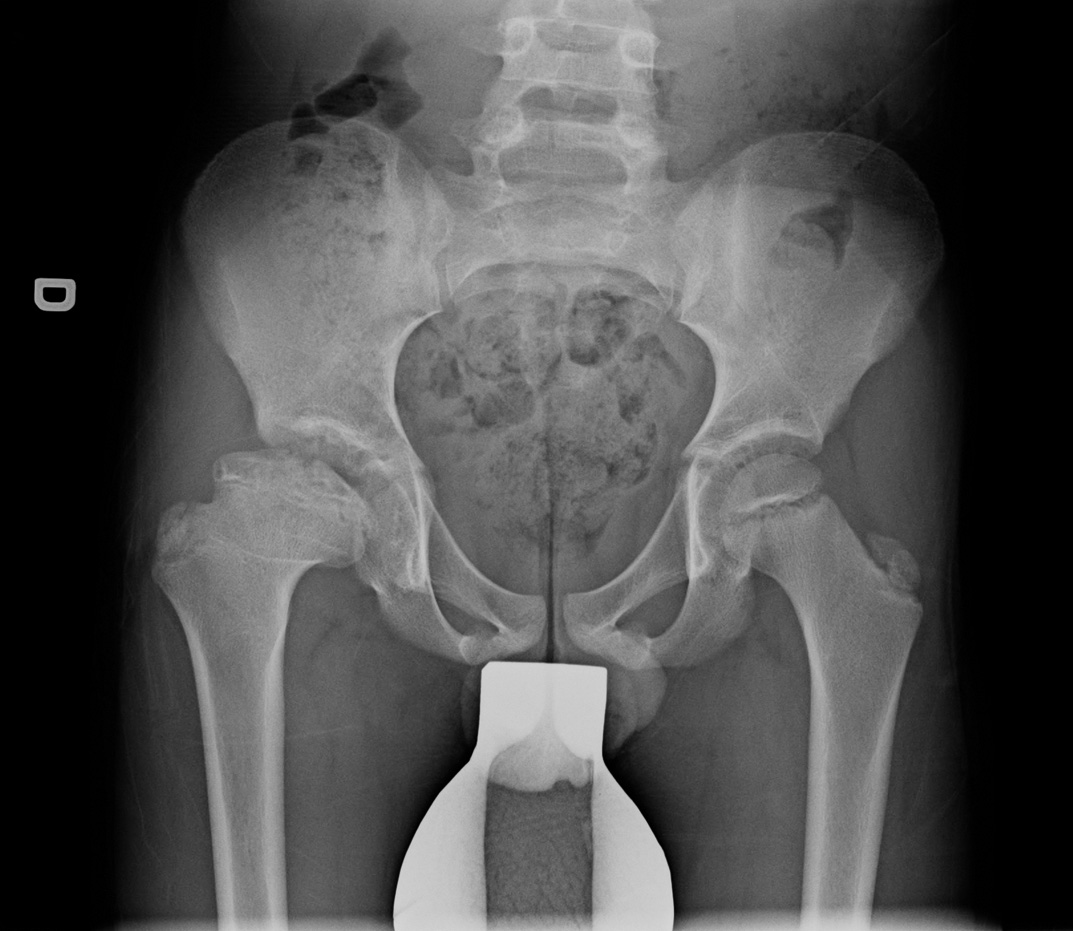

9-year-old male:

Follow-up of a Legg-Calvé-Perthes disease.

Legg-Calvé-Perthes disease

Bony irregularities

Slight progression of the femoral head ossification compared with the previous study.

Femoral head subluxation

We can see that the right femoral head is not fully covered by the acetabular rim on the right side as opposed to the left side.

Frog-leg